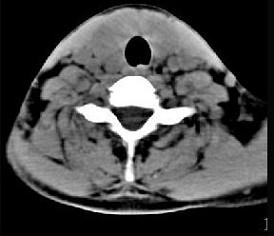

问题 40岁,女性患者,双侧甲状腺肿大,CT扫描如图所示,请选择最佳答案 ( )

选项 A、亚急性甲状腺炎 B、甲状腺瘤 C、甲状腺癌 D、甲状腺炎(桥本) E、弥漫性甲状腺肿

答案 D